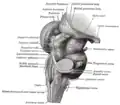

Mésencéphale et rhombencéphale (vue postero-latérale).